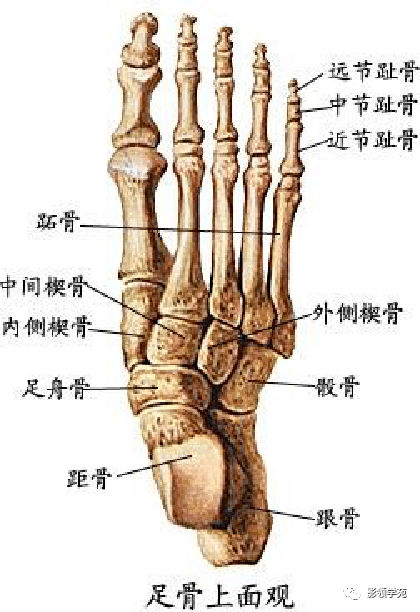

骨骼系统

骨骼系统